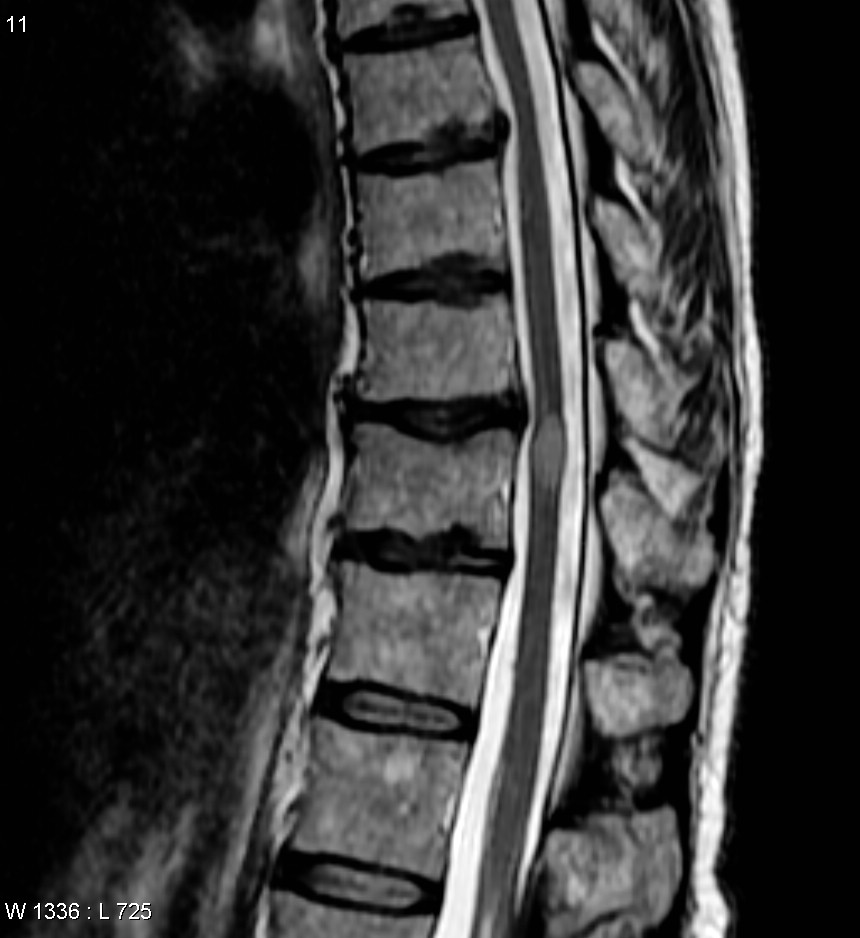

척수염은 감별해야 할 질환이 매우 다양하다. 진단을 위해서는 우선 발병 유형(급성인지, 아급성/만성인지)과 관련 증상을 파악하는 것이 중요하다. 통증, 발열, 불쾌감, 체중 감소, 피부 발진 같은 전신 증상이 있는지 확인하면 원인을 찾는 데 도움이 될 수 있다. 척수염 진단은 문제가 되는 척수의 위치를 정확히 찾아내고, 뇌나 신경근 질환이 아님을 확인하는 과정이다. 이를 위해 자세한 병력 청취, 세심한 신경학적 검사, 그리고 자기 공명 영상(MRI)을 이용한 영상 검사가 필수적이다.[11]

특히 갑자기 발병한 급성 척수염의 경우, 수술이 필요할 수 있는 구조적 문제나 다른 부위로 퍼진 질환(파종성 질환)이 있는지 확인하기 위해 척추 전체 MRI 검사가 필요하다.[11] MRI 검사 시 가돌리늄이라는 조영제를 추가로 사용하면 진단의 정확도를 더욱 높일 수 있다. 또한 중추 신경계(CNS) 침범 범위를 확인하기 위해 뇌 MRI 검사가 필요할 수도 있다.